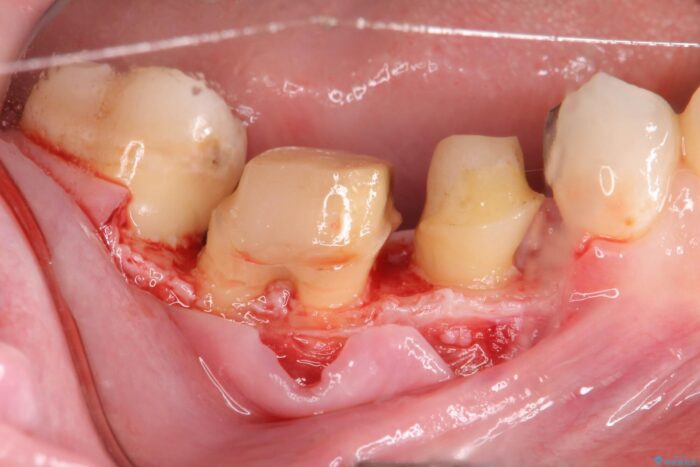

虫歯を丁寧に除去し、歯周外科を用いて周囲の歯ぐきの炎症を除去します。その後、清掃性の高い精密なセラミック治療をおこなっていきます。